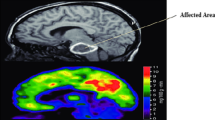

Individuals with Motor Neuron Disease were unable to move from one place to another because it gradually reduced all the voluntarily movement due to the degeneration of upper and lower motors neurons. The solution to this problem was to develop rehabilitating devices using biosignals. In this study, we have designed and developed electrooculogram-based wheelchair control using Cross Power Spectral Density. The convolution neural network to verify the performance and recognition accuracy of the wheelchair navigation in the indoor environment by using four trained users and four untrained users between the different age-groups and obtained the accuracy of 91.18% and 86.88% by using four fundamental tasks. From the indoor performance, the subject S4 from trained users outperforms all the trained subjects with an average classification accuracy of 93.51%. To verify the recognition accuracy, we conducted the online performance from the online performances subject S4 from trained subjects outperforms remaining trained subjects at the same time the subject S6 from untrained subjects outperforms all the untrained subjects. From the entire study, we analyzed that classification accuracy of subjects S4 was appreciated compared to other subjects. Through the research, we confirmed that the entire trained subject’s performance was maximum compared to the untrained subjects in all the circumstances.

Zarei S, Karen C, Luz R, Kelvin D, Orleiquis G, Pablo FA, Wilfredo P, Daud L, Gloria O, Angel C (2015) A comprehensive review of amyotrophic lateral sclerosis. Surg Neurol Int 6:171

Grollemund V, Pradat PF, Querin G, Delbot F, Le Chat G, Pradat-Peyre JF, Bede P (2019) Machine learning in amyotrophic lateral sclerosis: achievements, pitfalls, and future directions. Front Neurosci 13:1–28

Gordon J, Lerner B (2019) Insights into amyotrophic lateral sclerosis from a machine learning perspective. J Clin Med 8(10):1578

Arthur KC, Calvo A, Price TR, Geiger JT, Chio A, Traynor BJ (2016) Projected increase in amyotrophic lateral sclerosis from 2015 to 2040. Nat Commun 7(1):1–6